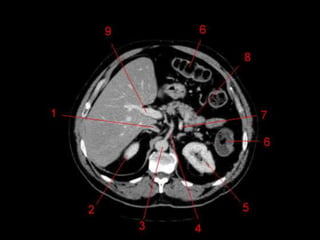

• TC: Tres fases

– Arterial (10 a 20 segundos)

– Fase venosa portal ( 30 segundos )

– Fase venosa hepática (60 segundos)

Técnicas de Imagem •US: Primeiro exame pedido ao: 1) dor no hipocondrio direito; 2) testes de função hepáticas anormais; 3) suspeita de malignidade. • TC: Tres fases – Arterial (10 a 20 segundos) – Fase venosa portal ( 30 segundos ) – Fase venosa hepática (60 segundos) • TC Portografia: Metastases.